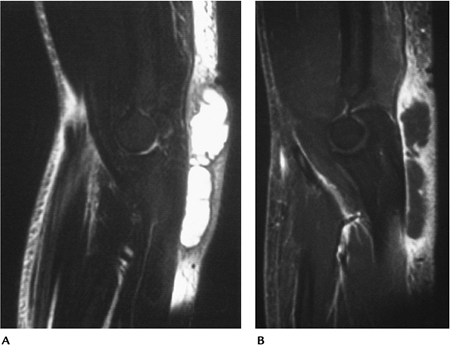

P.557

FIGURE 8-34 Gout. (A) AP and lateral radiographs demonstrate prominent nodular swelling (arrows). Sagittal (B,C)

post-contrast fat-suppressed T1-weighted images demonstrate enhancement of the distended bursal lining caused by gouty inflammation. |